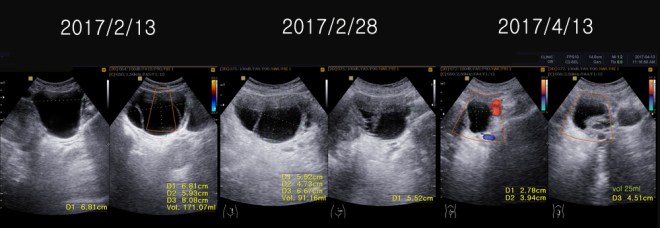

환자는 1년 전에 난소의 양성종양으로 수술을 받았던 경험이 있고, 이번에도 유방수술 이후에 초음파를 보니 83mm x 61 mm x 58 mm의 약 8cm x6cm 정도의 격벽으로 분리된 cystic mass 즉 액상의 종양이 보였고, 또한 13mm, 15 mm의  mass도 발견되었다(2017년 1월 26일 검사).

1. 6.8cm x 5.9cm x 8.1 cm 크기의 여러 개로 갈라진 격벽을 가지고 있는 액상의 부위가 왼쪽 자궁주위 조직에 보이는데 양성의 혹으로 보인다.

1. 6.8cm x 5.9cm x 8.1 cm 크기의 여러 개로 갈라진 격벽을 가지고 있는 액상의 부위가 왼쪽 자궁주위 조직에 보이는데 양성의 혹으로 보인다 (volume 171 CC).

이후에 이 환자를 본원의 한방 항암약물로서 소양인에게 적합한 R0052와 위에서 설명했듯이 양방의 소양인 치료법인 femara+ arimidex 요법과 더불어서 철저한 식이요법을 시행시켰고, 약 12일 뒤인 2월 28일 다시 초음파 체크를 하였다. 이같이 빠른 체크를 2주 내에 하는 이유는 약물의 방향이 맞는가 약물의 농도가 맞는가를 알기 위해서이다. 그 결과는 다음과 같다.

2주간의 한양방 결합요법의 결과 3항에서 보듯이 약 7mm 정도의 전에 잔류 종양으로 보이던 부분이 약간 줄어들었고, 자궁주위에 있던 난소의 종양은 6.8×5.9x 8.1cm의 크기가 5.5×4.7×6.7cm 로 체적대비해서 171 cc가 91 cc로 100%의 종양이 53%로 절반 가량이 줄어들었고, 자궁내벽의 비후는 여전히 보이고, 3cm 크기의 근종으로 보이는 종양은 차이가 없었다.

이후 환자는 2017년 4월 13일 치료 시작한지 2달 만에 다시 에스트로겐 수치와 초음파 검사를 하게 되었다.

1-9

4월 13일 초음파 결과에 의하면 이전에 보이던 우측의 수술부위와 우측 액와림프절 수술부위의 섬유화가 많이 줄었고(2), 선 같은 액상의 7mm 크기의 근육 내의 nodule도 섬유화처럼 변모되었고(3), 골반에 있던 이전이 91cc의 다격벽의 난소종양도  25CC로 줄어들었다. 또한 자궁하부에 보이던 근종으로 의심되는 부분도 3cm에서 2cm로 줄어들었다. 또한 에스트로겐 검사도 이전에 1000이 넘던 수치가 40대로 떨어져서 확연한 에스트로겐의 감소를 알 수 있다.

1. A multiseptated cystic lesion in the left parametrium, cystic ovarian tumor, muchmore regressed(5.5×4.7×6.7cm/91ml ->2.8×3.9×4.5/25ml)

171 ml                                               91 ml                                           25ml